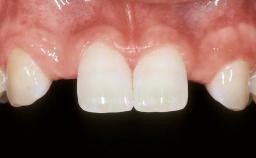

ITI Curriculum FL: Patient Assessment Case 10

Example intended for case-based discussion regarding patient assessment, diagnosis and determination of risk and complexity.

Esthetic Risk Assessment

| Patient's Esthetic Expectations | Low | Medium | High |

| Lip Line | No exposure of papillae | Exposure of papillae | Full exposure of mucosa margin |

| Periodontal Phenotype | Low-scalloped, thick | Medium-scalloped, medium-thick | High-scalloped, thin |

| Shape of Tooth Crowns | Rectangular | Triangular | |